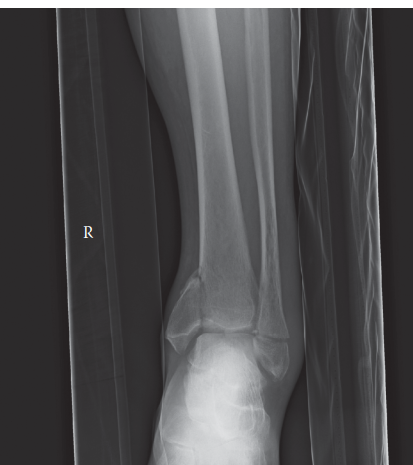

A 19-year-old male is brought in after an ATV accident when he was off-roading on his grandparent’s farm. He …

Can you describe the radiograph? This is an AP and lateral radiograph of the left ankle. It shows a bimalleol…